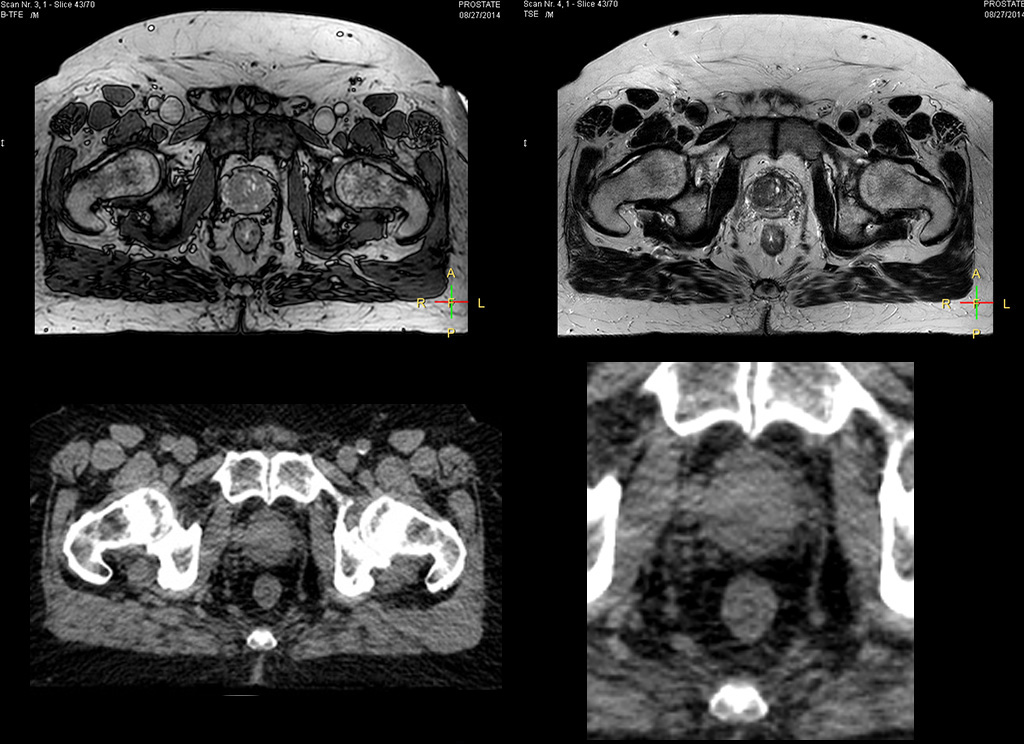

Beaumont Health System (Royal Oak, Michigan, USA) is one of the largest health systems in the USA, with eight hospitals and 153 outpatient sites, a medical school and a research institute. The Radiation Oncology (RO) department houses a dedicated Ingenia MR-RT solution that is routinely used for clinical and research MR-RT activities. “The main reason to integrate MR imaging in RT planning is the superb soft tissue contrast that allows detailed delineation of tumors and healthy organs, which is crucial for RT planning,” says Craig W. Stevens MD, PhD. “MR also provides information on functional and biological activities in tumors, background tissue and normal organs, which may also be used in RT planning,” says physicist Di Yan, DSc, FAAPM.” “We currently use MR-RT mainly in the abdomen and pelvis region: prostate, colorectal, pancreatic, cervical, and liver. Also in the brain, we are starting to use it,” says Dr. Yan.

“The biggest problem for CT-based planning, especially in prostate, is you can’t see the cancer very well,” says Dr. Stevens. “On CT it can be quite challenging to see the edge of the prostate especially at the apex. When the edge of the prostate can’t be delineated well on CT, radiation oncologists will increase their margins a little bit so they don’t miss it, but that can also increase toxicity.” “Using MR, the prostate is well delineated. We quickly see the edges of cancerous tumors like in prostate cancer, and as normal structures can be defined, we can optimize the treatment plan to protect these organs and their normal function. This can potentially improve the outcome. And it improves workflow as well. We can contour more quickly, confident that the tumor is going to be in the field.” “The Ingenia 3.0T MR scanner provides high resolution allowing us to make scans fast for the patients. It also gives the potential to include methods like MR spectroscopy and diffusion weighted Imaging, which we’re in the process of doing right now,” Dr. Stevens adds.

“When a patient registers, first CT simulation and MR simulation are done, followed by CT-MR registration on Pinnacle3. Then the target and normal organ delineation is performed on MR images. Meanwhile we create a reference CT image for online treatment and localization correction. During the treatment phase we can perform additional MRI scans to visualize the anatomy changes and create an adaptive plan. This plan basically adapts the treatment plan to the changes.” “Along with its great benefits, MR has introduced some new challenges,” Dr. Stevens says. “Radiation therapy teams generally have no experience with MR. The Philips training helped us to implement fully the things we can do with the Ingenia MR-RT system. So the training, as well as having a good MR physicist, is critical.”